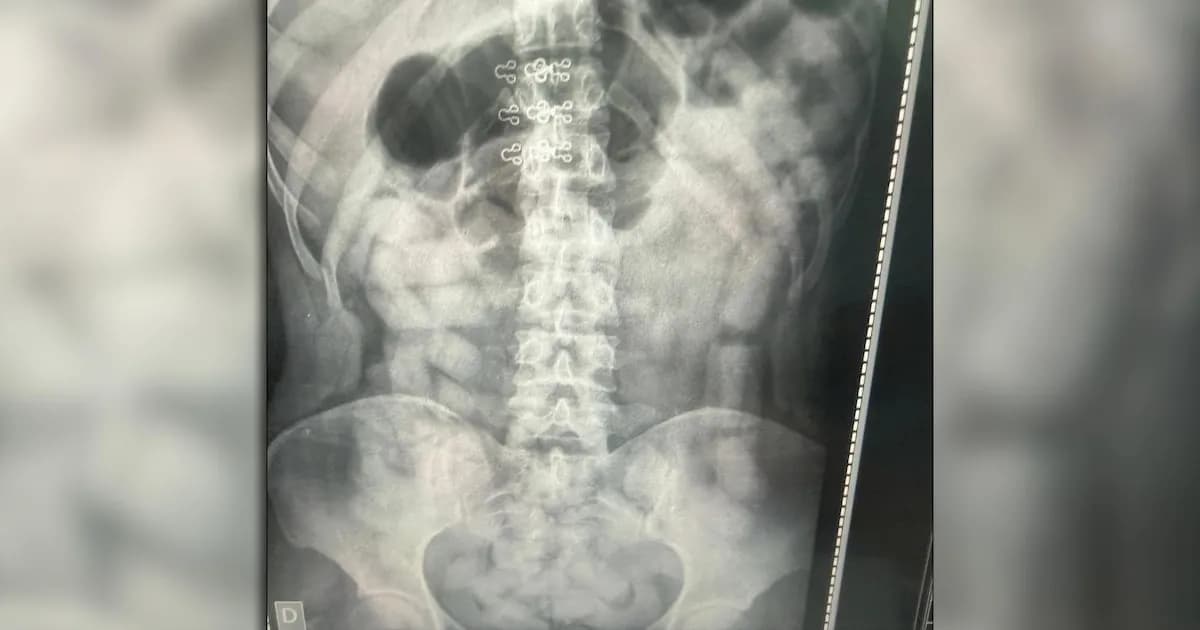

Durante la inspección física y documental, los agentes encontraron un total de 249 envoltorios que contenían más de 3 kilos de cocaína, escondidos entre las pertenencias de tres mujeres. Este descubrimiento inicial llevó a la realización de radiografías a todos los pasajeros al día siguiente, lo que reveló la presencia de cuerpos extraños en el abdomen de seis personas: cuatro mujeres y dos hombres. La técnica utilizada es sumamente arriesgada para la salud, y resalta la gravedad de la situación en la que se encuentran quienes optan por este método de transporte de estupefacientes.

Los seis individuos identificados fueron trasladados a hospitales de la zona, donde bajo custodia médica, expulsaron un total de 503 cápsulas que contenían más de 6 kilos de cocaína. En total, la división de Criminalística y Estudios Forenses contabilizó 752 cápsulas, con un peso total de 10 kilos 316 gramos de la droga. Este tipo de procedimientos no solo son alarmantes por la cantidad de droga involucrada, sino también por los riesgos que corren los pasajeros que se ven obligados a participar en este tipo de actividades ilícitas.